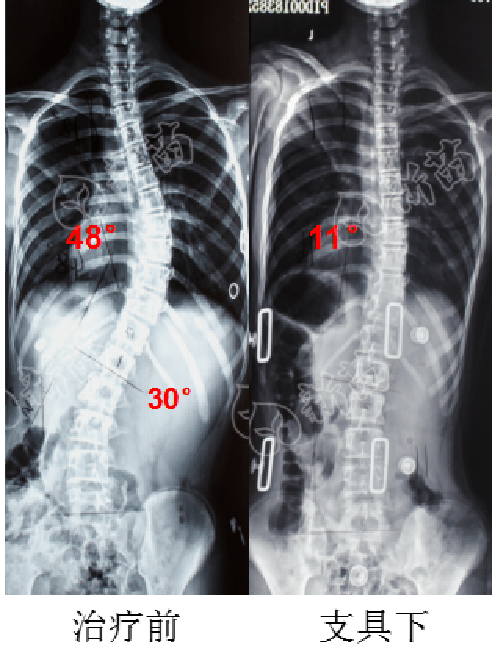

治疗过程(4)左右腰线不对称,左腰线凹陷(3)右剃刀背(2)肩胛骨不对称(1